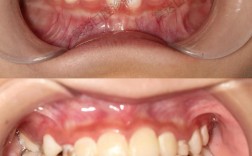

深覆合是口腔正畸中常见的错颌畸形类型,主要表现为上前牙切缘盖过下前牙牙冠过多,垂直距离过小,可能伴随下颌后缩、面部比例不协调等问题,长期存在可能导致咬合创伤、颞下颌关节紊乱甚至消化功能异常,其矫正过程需结合患者年龄、错颌程度、骨骼条件等因素综合设计,通常需经历术前评估、方案设计、主动矫正、保持巩固四个阶段,每个阶段环环相扣,以确保矫正效果稳定且兼顾功能与美观。

矫正前需进行全面系统的检查,这是制定个性化方案的前提,临床检查中,医生会通过视诊观察牙齿排列、咬合关系、面部对称性及唇部闭合情况,用探针检查牙周健康状况,通过咬合纸记录早接触点,初步判断深覆合的类型(前牙深覆合可能伴随深覆盖或中性关系),影像学检查是核心环节,包括全景片观察全口牙根形态、牙槽骨情况及发育状况,头颅侧位片进行X线头影测量,分析骨骼型(如骨性深覆合常伴有上颌前突或下颌后缩)、牙齿倾斜度、 Spee曲线深度(深覆合患者Spee曲线通常过深,可达7-10mm,正常应≤2mm)及面部软组织轮廓,还需取研究模型,利用模型测量牙齿拥挤度、 Bolton指数等,辅助判断是否需要邻面去釉或拔牙矫正。

这是矫正深覆合的核心阶段,重点通过“压低上前牙、伸长下前牙、调整颌平面”三方面改善垂直距离。